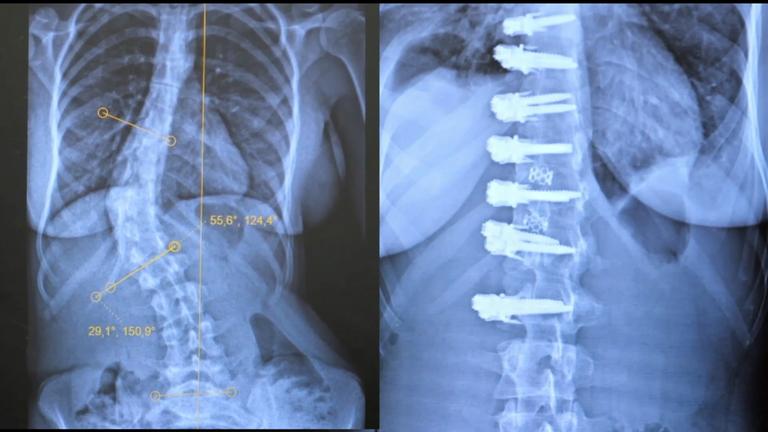

Ziel der Operation ist es, die Spinalkanäle freizulegen, die eingeengten Nervenwurzeln zu entlasten (Dekompression), den verrutschten Wirbel in die richtige Position zu ziehen (Reposition), um die Wirbel dann zu versteifen und zu stabilisieren (Wirbelfusion).

Dafür werden während der Operation unter Röntgenkontrolle spezielle Titanschrauben in den verrutschten und in den benachbarten Wirbel eingebracht. Mit einer speziellen Vorrichtung wird der verrutschte Wirbel in die richtige Position gezogen und mit dem benachbarten Wirbel mit Titanstangen verbunden.

Zur Stabilisierung wird die Bandscheibe des betroffenen Wirbelsegments entfernt und ein Platzhalter (Cage) eingebracht. Dieser wird mit Knochenmaterial befüllt, um ein stabiles Zusammenwachsen der Wirbel zu erreichen.